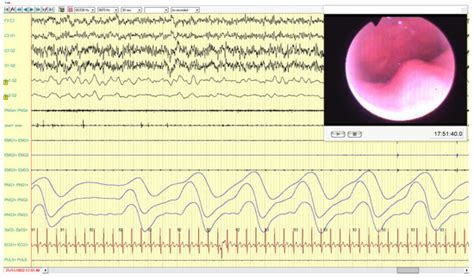

Computed Tomography versus Sleep Endoscopy (DISE) to Predict the ...

Analysis of the Effects of a Mandibular Advancement Device on Sleep ...